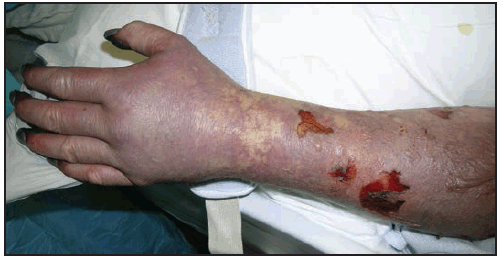

Severe, late-stage manifestations of RMSF include meningoencephalitis, acute renal failure, ARDS, cutaneous necrosis, shock, arrhythmia, and seizure. Features of late illness might be confused with other diseases or syndromes. For example, RMSF-associated cutaneous necrosis and gangrene might be difficult to distinguish clinically from purpura fulminans associated with meningococcemia (105). RMSF-associated neurologic manifestations, renal failure, and thrombocytopenia have led to confusion with the diagnosis of thrombotic thrombocytopenic purpura (TTP) (106–108). RMSF-associated vasculitis has been confused with idiopathic, acute vasculitides, such as Kawasaki disease in pediatric patients. RMSF might also mimic bacterial or viral meningoencephalitis (109). Focal neurologic deficits, including cranial or peripheral motor nerve paralysis, or sudden transient hearing loss can occur (110–112).

Long-term neurologic sequelae of RMSF include cognitive impairment; paraparesis; hearing loss; blindness; peripheral neuropathy; bowel and bladder incontinence; cerebellar, vestibular, and motor dysfunction; and speech disorders (7,110,121–124). These complications are observed most frequently in persons recovering from severe, life-threatening disease, often after lengthy hospitalizations, and are most likely the result of R. rickettsii-induced vasculopathy. Cutaneous necrosis and gangrene ( Figure 23) might result in amputation of digits or limbs (105). Long-term or persistent disease caused by R. rickettsii has not been observed.